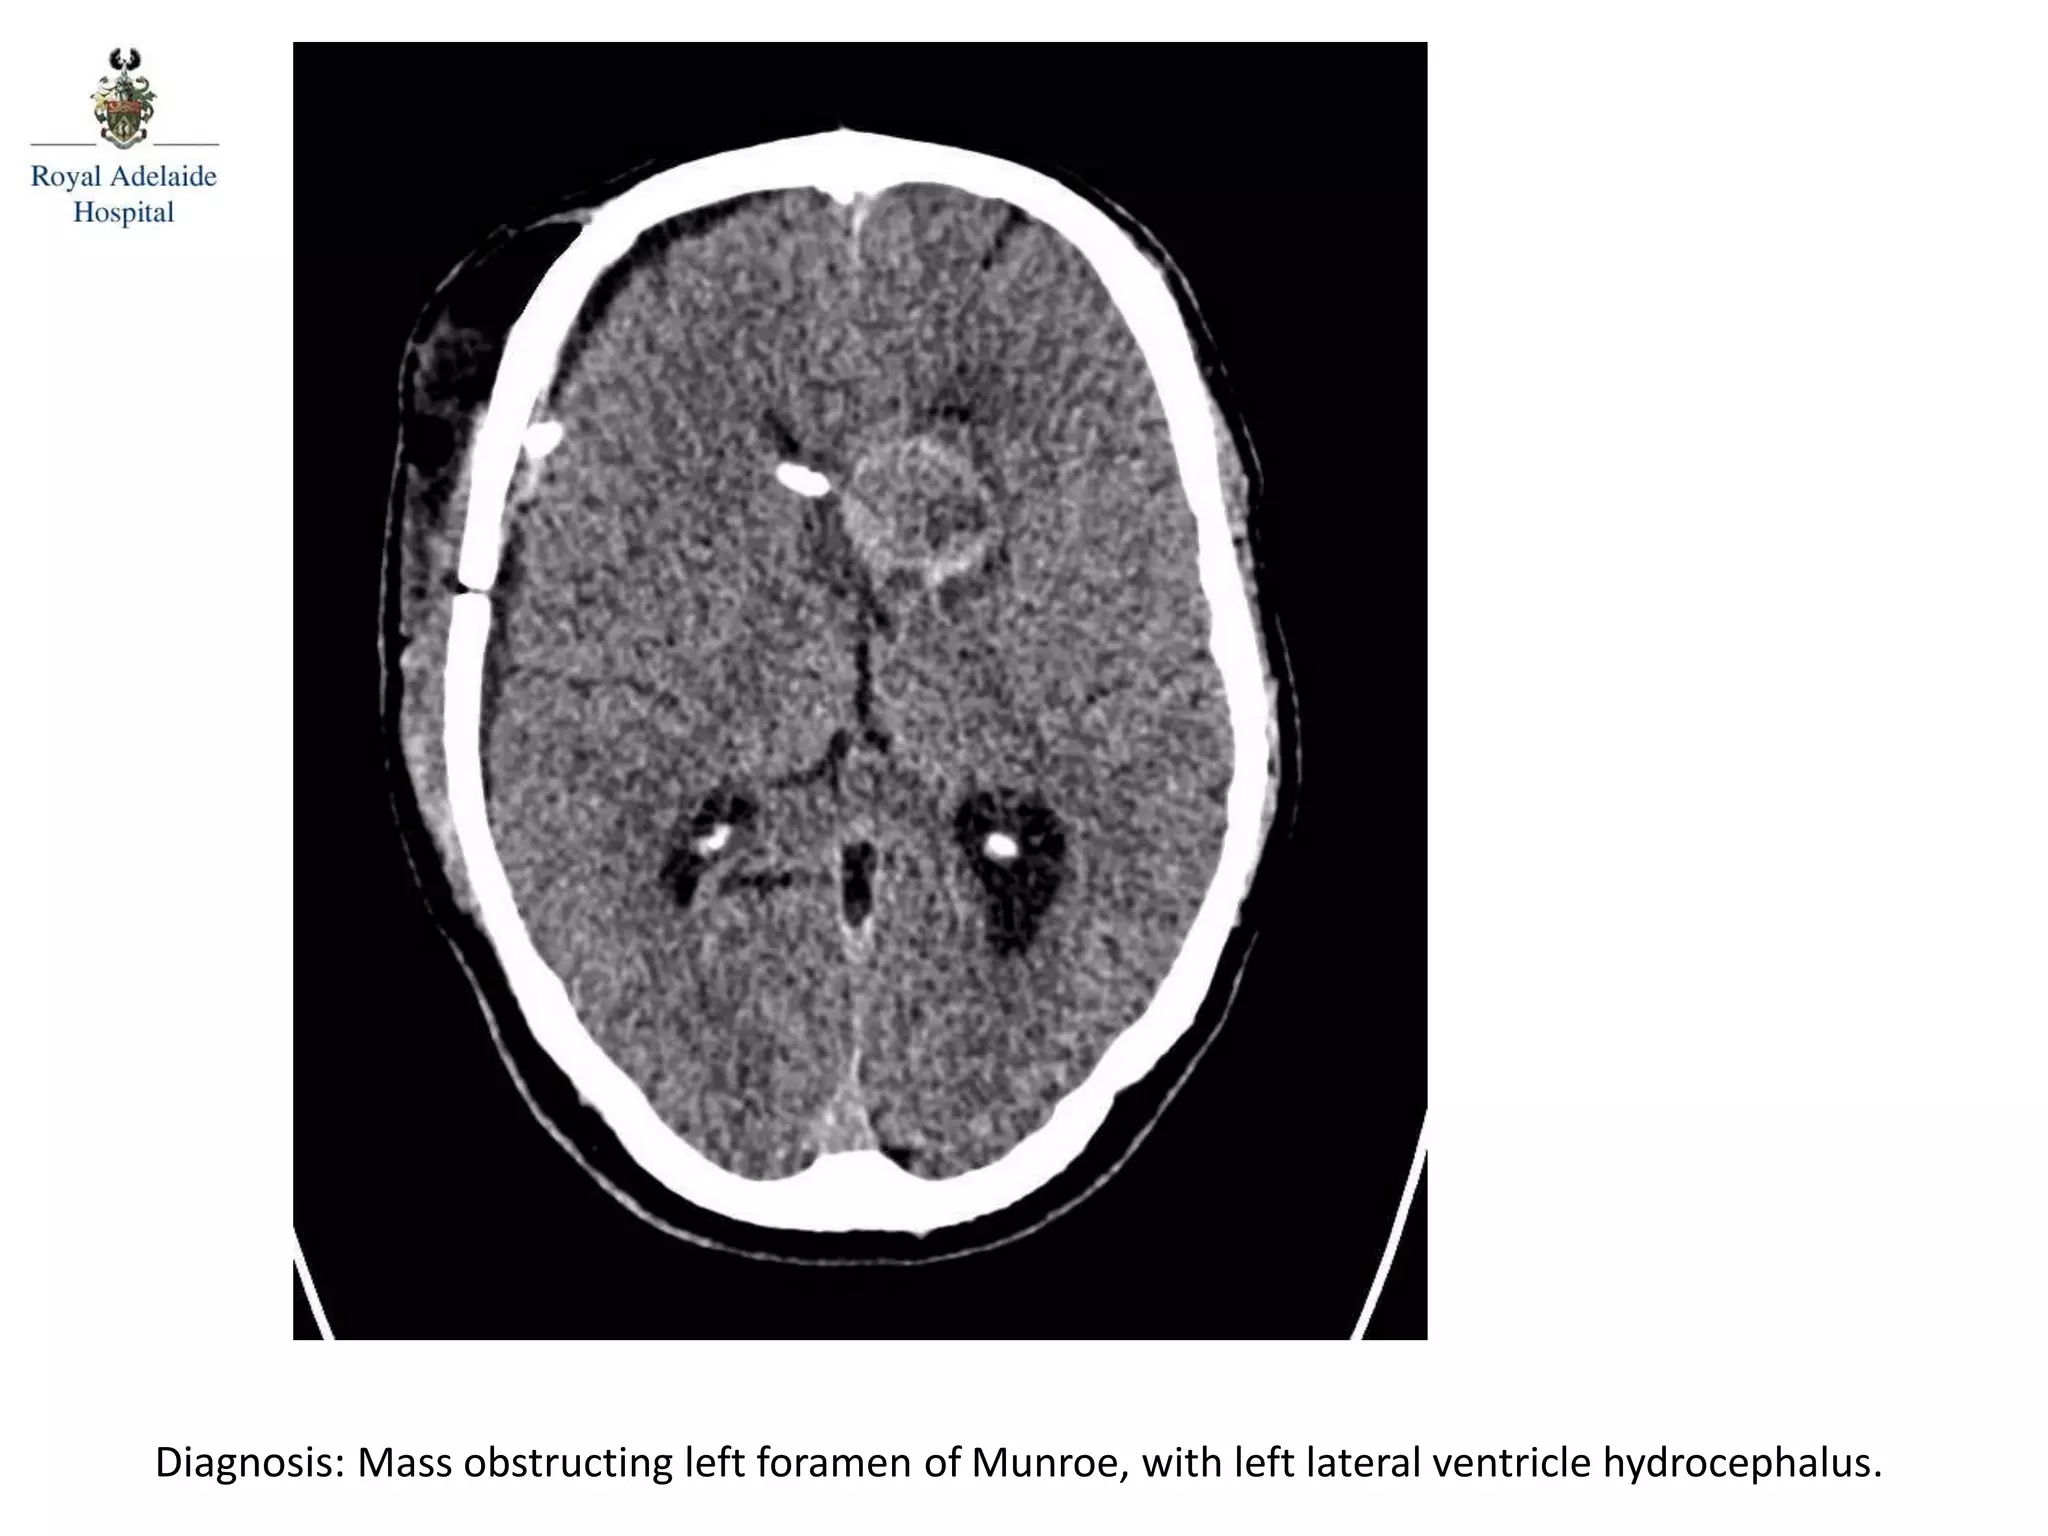

The document outlines multiple diagnoses from head CT cases, including small left basal ganglia bleed likely due to hypertension, various types of subdural and subarachnoid hemorrhages, and evidence of hydrocephalus. It details traumatic origins of some hemorrhages and notes obstructing masses and atrophic changes. Overall, there are significant findings indicating complications related to cerebral hemorrhages and ventricular enlargement.